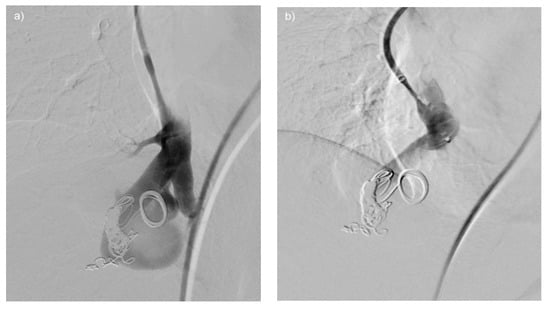

Figure 1. Cerebral DWI (b = 800) demonstrating subacute cerebral ischemia, in this case prior to embolization of multiple PAVMs. The newly developed lesion arose between screening for PAVM and the day of interventional therapy, but the patient did not exhibit any clinical signs or symptoms. This example highlights the importance of DWI for the detection of pre-existing cerebral ischemia, as well as peri-interventional cerebral insult.